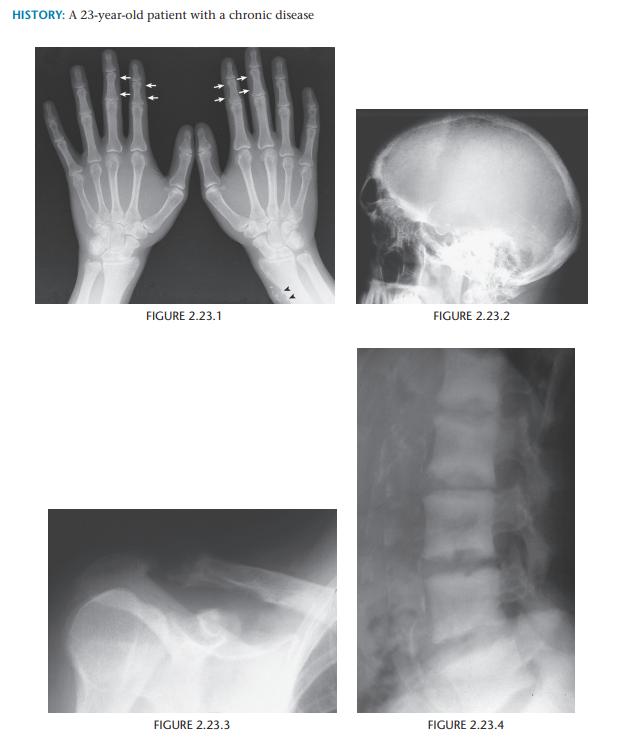

Secondary Hyperparathyroidism

Subperiosteal resorption along the radial aspects of

the second and third middle phalanges of the hand is

diagnostic of hyperparathyroidism.

Paget’s Disease

Characteristic, but not entirely pathognomonic, patterns of Paget disease include the flame-shaped lucency within the long bones, the “ivory” and “picture

frame” vertebral body, and osteoporosis circumscripta or cotton-wool appearance of the skull